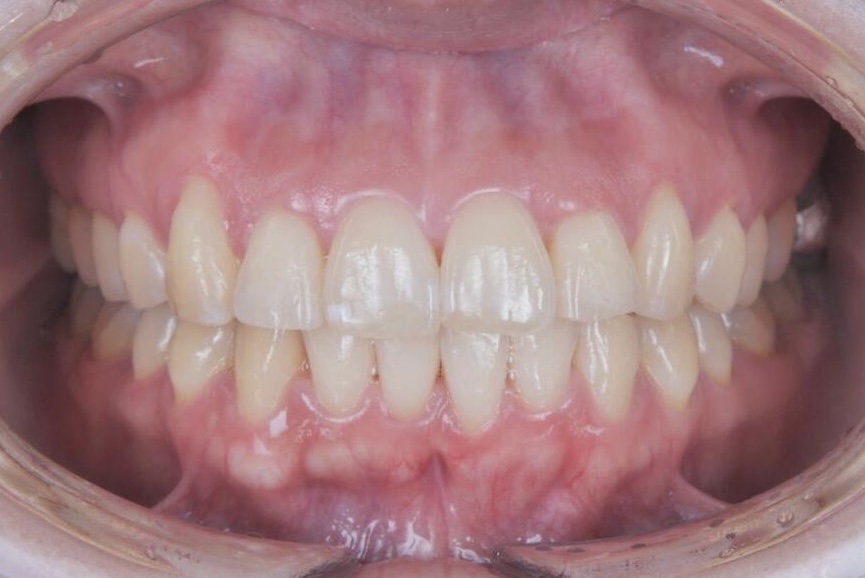

その結果、前歯の突出感や下の前歯のガタつきが改善し、前歯でしっかり噛める機能的な咬み合わせを獲得することができ、見た目と機能の両面で良好な結果が得られた症例です。

AFTER

| 年齢・性別 | 30代女性 |

|---|---|

| 主訴 | 出っ歯が気になる、前歯で噛めない |

| 施術内容 | 歯全体のマウスピース矯正システム「インビザラインフル」を用いた治療 |

| 治療期間 | 1年10ヶ月 |

| 費用 | 924,000円(税込) |